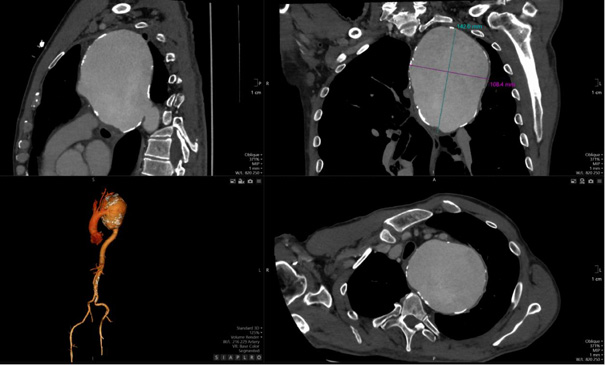

The detection of a mediastinal mass prompted differential diagnostic considerations, primarily focusing on two major possibilities: (1) mediastinal tumor formation associated with lymphocytic infiltration due to leukemia or other oncological masses, and (2) a giant vascular aneurysm. To delineate the etiology, a two-dimensional CT scan of the thoracic aorta was performed, as shown in Figure 2, revealing a large aneurysm in the distal post-arch segment of the descending aorta. The observed mass corresponds to a giant aneurysmal dilation.

The aneurysm measured 14.08 × 10.04 cm in its maximum transverse diameters. No chronic thrombus was identified within the tunica media, nor was there any evidence of dissection. The proximal ascending aorta measured 38 mm in diameter. Figure 3, which depicts a three-dimensional CT reconstruction, delineates the anatomical relationship of the aneurysm with the aortic arch, the left subclavian artery, and the descending thoracic aorta. The aneurysm was localized, with no involvement of the proximal left subclavian artery or its orifice. The distal portion of the aneurysm did not extend to spinal or intercostal branches. The remainder of the aorta, including the abdominal segment, appeared normal. The primary clinical impact of the aneurysm was attributed to a significant mass effect, leading to compression of the trachea and bronchi as well as potential irritation of the left phrenic nerve secondary to mediastinal compression.

CT angiography remains the gold standard for the diagnosis and assessment of the extent of GDTAA [21]. It allows high-resolution visualisation of the size and morphology of the aneurysm as well as the anatomical relationships with the adjacent structures [21]. In this case, CT imaging confirmed a massive aneurysm with significant displacement of the trachea and compression of the bronchi, thereby emphasising the crucial role of modern imaging in surgical planning [21].